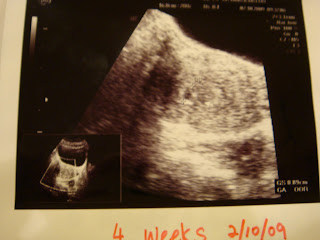

Ultrasound Scans

Gestational sac (GS): 0.89cm

GS: 1.92cm

Crown to Rump length (CRL): 0.71cm

We first saw the gynae on 2nd Oct when we were 4 weeks and the abdominal ultrasound (US) showed a gestational sac (GS) diameter of 0.89cm.

Second visit was on 5th Oct because of the dizzy spells caused by Progesterone pills and another US was done where GS was 1.03cm.

Third visit was today 14th Oct and an abdominal US showed a GS measuring 1.92cm (5weeks 5 days), but no heartbeat could be detected as it was still early. So we opted for a transvaginal US which showed a very clear picture of our baby, with a good strong heartbeat! It also showed that the crown to rump length (CRL) measured 0.9cm and baby was in fact 6 weeks and 4 days old! Our baby's growing on track! PRAISE THE LORD!!